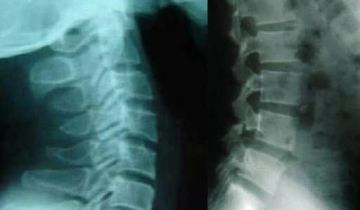

Chụp X-quang thoái hóa cột sống

Bệnh thoái hóa cột sống gặp phổ biến ở người trên 40 tuổi. Ngày nay, bệnh thoái hóa cột sống càng ngày càng trở nên phổ ...

Thoái hóa cột sống thắt lưng là gì?

Thoái hóa cột sống thắt lưng (Spondylosis) là một bệnh mãn tính khi đĩa đệm và khớp bị thoái hóa, xương phát triển trên ...